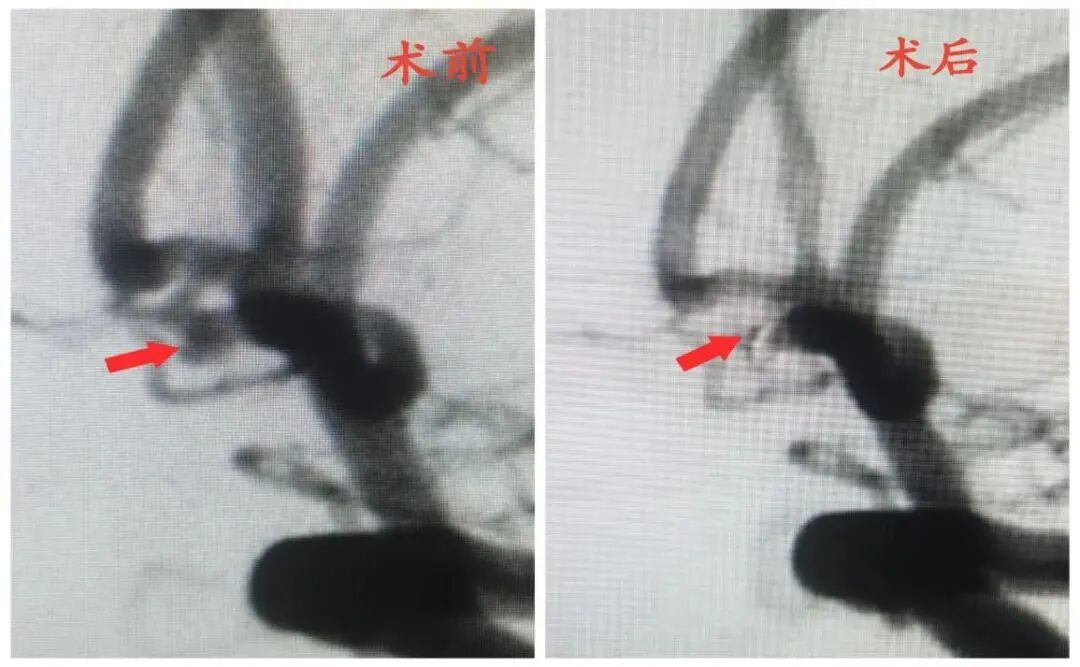

神经科急危重症诊治,尤其急性出血性、缺血性脑血管病及颅脑损伤抢救,脑血管病显微手术及介入诊疗(高血压脑出血显微镜/神经内镜下血肿清除术、急性脑血栓取栓术、脑动脉瘤栓塞术、脑血管畸形栓塞术、颅内动脉狭窄成形术、复合颈动脉斑块切除术、颈动脉及椎动脉狭窄支架置入术)。